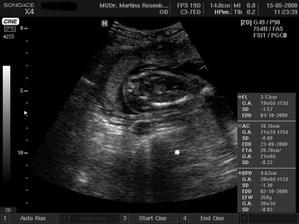

15.5. na kontrole vše v pořádku a asi opravdu budeme holčička, váhu máme 360 g a měříme 16 cm od temene hlavičky po prdelku. Příští kontrola 12.6. a o týden později 3D ultrazvuk...............